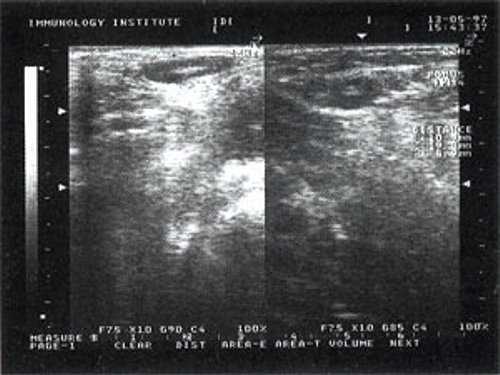

Практически во всех случаях дифференцировали лимфатический узел Кютнера (югулодигастральный), расположенный на границе средней и верхней трети шеи. Выявляемые лимфатические узлы имели размеры от 0,5 х 0,2 см до 2,3 х 0,8 см. УЗ-оценку производили после полипозиционного осмотра и нахождения самой длинной горизонтальной оси, что и принимали за максимальный поперечный диаметр. Большая часть лимфатических узлов (187) имели овальную форму с соотношением поперечного/переднезаднего более 1 (рис. 1 - 3). Тенденцию к округлению имели 30 лимфатических узлов, соотношение поперечного/переднезаднего приближалось к 1.

Рис. 1. УЗ-томограмма увеличенного реактивно измененного лимфатического узла: а - на фоне аденовирусной инфекции, б - после проведения противовоспалительного лечения